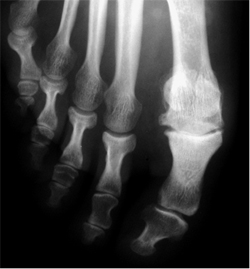

¿Qué es el hallux rígidus?

Es una limitación de la movilidad de la articulación metatarsofalángica del dedo gordo. Esta limitación altera el funcionamiento normal del pie y puede producir dolor. Cuando progresa, aparece una prominencia dorsal en esta articulación que puede ser muy dolorosa.

¿Por qué se produce el hallux rígidus?

Existen una serie de factores predisponentes como la excesiva longitud del primer metatarsiano, traumatismos repetidos, retracción de partes blandas, etc. El primer consejo que damos a nuestros pacientes es calzarse un zapato con una suela en balancín. Las inyecciones de ácico hialurónico pueden ser efectivas en el tratamiento de esta alteración.

Hay muchos tipos de cirugía para tratar el hallux rígidus. Cada especialista tiene sus preferencias en función de su formación y experiencia. El hallux rígidus puede tener diferentes grados evolución. Dependiendo del grado evolutivo puede ser necesario: resección protuberancia, osteotomías (cortes) de los huesos o fijación de la articulación.